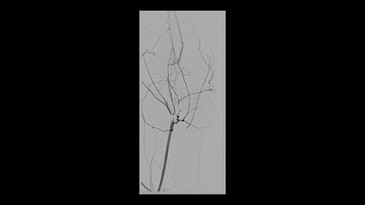

Klinik Görüntüler

-

İliyak stentlemesi